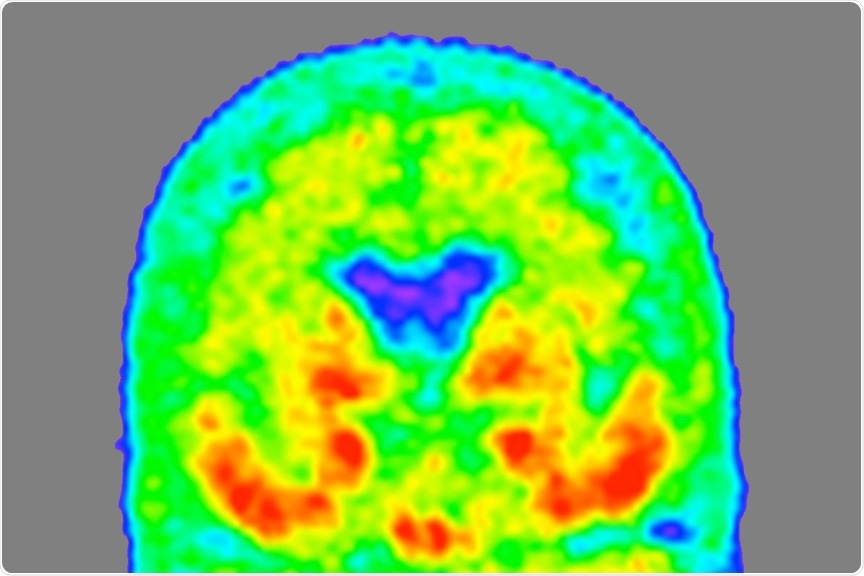

Image Credit: Tammie Benzinger/Knight ADRC

Currently, positron emission tomography (PET) scans are required to detect tau tangles in the brain. However, these are time-consuming and expensive. The identification of the MTBR tau fluid biomarker will allow scientists to develop more accessible, cost-effective testing. Bateman and his colleagues are currently working on establishing a diagnostic blood test with the help of this biomarker.